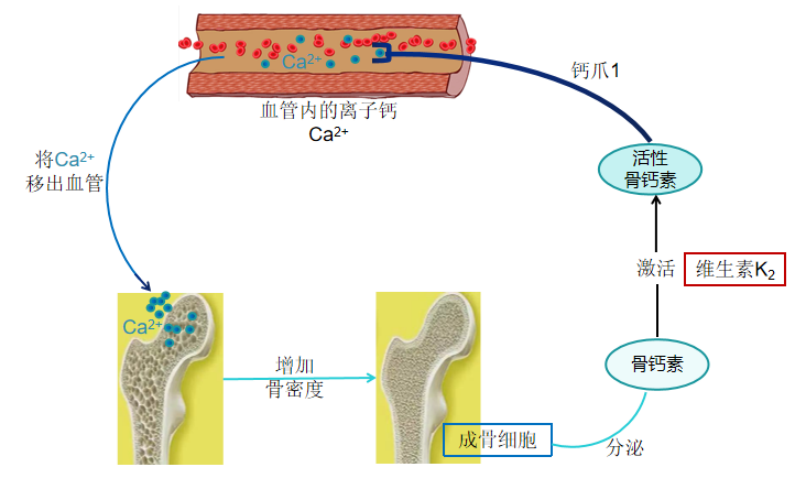

(2)骨钙素

成骨细胞分泌胶原纤维,叫类骨质,柔韧而富有弹性。同时成骨细胞还分泌骨钙素入血。骨钙素的任务是把血液中的离子钙抓住,送进骨质,融入到类骨质中,这样柔韧的类骨质就变成了坚硬的骨质。初分泌入血的骨钙素是不具活性的,没有捕获钙的能力,必须将它们激活,才能行使捕获离子钙的职责。骨钙素的激活剂就是维生素K2。

维生素K2激活骨钙素示意图

(3)维生素K2激活骨钙素领钙入骨

维生素K2能激活血液中的骨钙素,撮合骨钙素与离子钙结成终生伴侣,并把离子钙领回家。骨骼才是离子钙的最后归宿,从此离子钙就结束了流浪生涯,改名骨钙,成为骨骼强大的中坚力量。

维生素K2激活骨钙素示意图